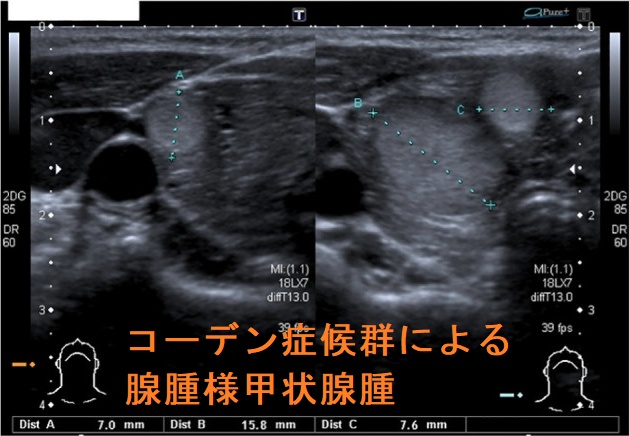

コーデン(カウデン,Cowden)症候群は常染色体優性遺伝性のPTEN遺伝子変異によるPTEN過誤腫症候群。73-80%に甲状腺腫瘍が発生し、全ての甲状腺細胞にPTEN遺伝子変異があるため甲状腺全摘出①甲状腺良性結節(腺腫様甲状腺腫・良性濾胞腺腫)70%②甲状腺分化癌(甲状腺乳頭癌・甲状腺濾胞癌)3-10%。ポイツ・ジェガーズ症候群(Peutz-Jeghers症候群)も常染色体性優性遺伝性で、合併する甲状腺分化癌は通常型と比べて悪性度高い。遺伝性非ポリポーシス大腸がんで甲状腺癌の合併あり。鋸歯状ポリポージス症候群は甲状腺乳頭癌と同じBRAF変異。

コーデン(カウデン,Cowden)症候群の73-80%に甲状腺腫瘍が発生。

- 甲状腺良性結節(腺腫様甲状腺腫・良性濾胞腺腫)70%

- 甲状腺分化癌(甲状腺乳頭癌・甲状腺濾胞癌)3-10%、※20%との報告も[Eur Thyroid J. 2020 Sep;9(5):243-246.]

腺腫様甲状腺腫・良性濾胞腺腫

コーデン(Cowden)症候群による腺腫様甲状腺腫を認めた場合、甲状腺分化癌(甲状腺乳頭癌・甲状腺濾胞癌)が発生する、あるいは既に合併している可能性があるため、甲状腺全摘出します。多発する腺腫様結節のいずれが、どの部分が癌化しているか事前に同定するのは困難で、しかも全ての甲状腺細胞がPTEN遺伝子変異を持っている限り、いつか、どれかが癌化する危険があります。